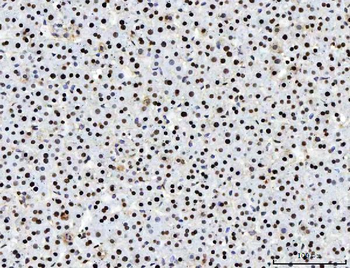

10 μg, 100 μgACTN2 Antibody / Alpha Actinin 2 / Sarcomeric Alpha Actinin [orb640016]

IHC-P, WB

Human

Mouse

Monoclonal

Unconjugated

20 μgACTN2 Antibody / Alpha Actinin 2 / Sarcomeric Alpha Actinin [orb640017]

IHC-P, WB

Human

Mouse

Monoclonal

Unconjugated

20 μg